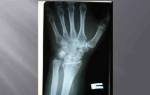

- Ультразвуковое сканирование вен нижних конечностей — определяет наличие тромбов и место их локализации.

- Рентгенограмма органов грудной клетки — для исключения легочной формы туберкулеза.